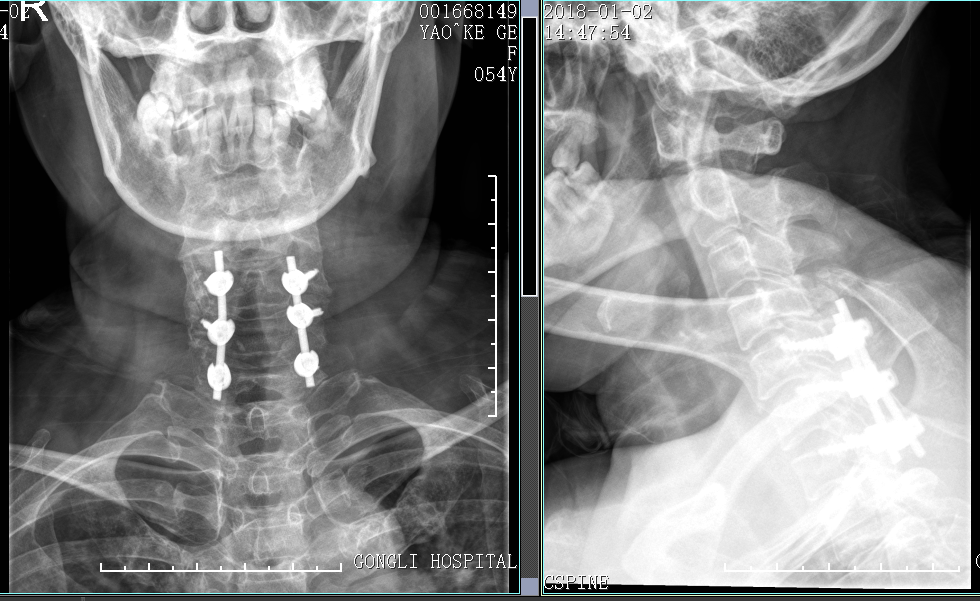

术后X片